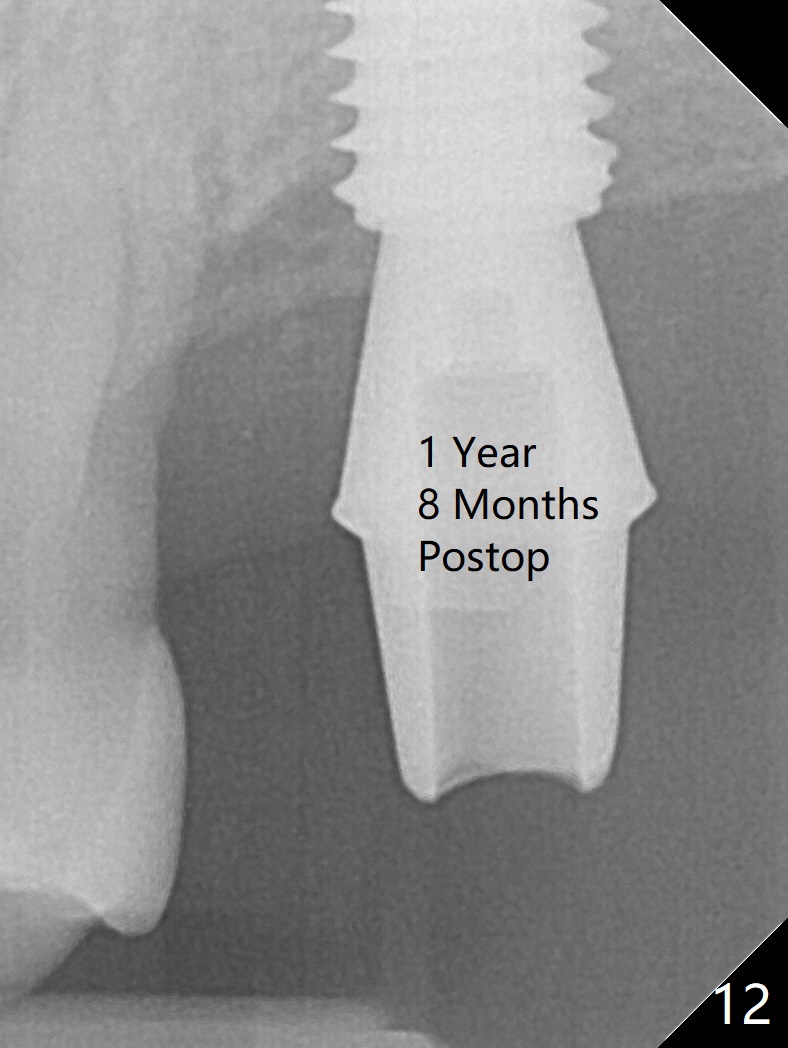

Although the buccal (Fig.1 (mesial view of the extracted tooth #15): B) root is larger than the palatal (P) one, the palatal socket is larger than the buccal one (Fig.2 white area) because of the bone loss of the former. For better restoration, osteotomy (Fig.2 red line) is initiated in the buccal slope of the septum (S) so that the final osteotomy is in the middle of the whole socket (Fig.3 red box). In fact a 3 mm stopper is not used because of the slope and the clumsy stopper. Stopper would be indicated if the bottom of the bone were flat. At first a 4x10 mm dummy implant is placed with stability (Fig.4). After further osteotomy and sinus lift (Fig.6 red dashed line: sinus floor), a 5x10 mm implant is placed with 30 Ncm, followed by insertion of a 5.2x8(2) mm temporary abutment (Fig.5,6). The latter holds an immediate provisional and Vanilla Graft/Osteogen (Fig.7 *) in place (^: distal crestal bone). Although the bone looks normal around the implant 7.5 months postop (Fig.4), the implant is unstable, probably due to the large preexisting defect. In contrast the implant placed at the healed site of #3 is stable 6.5 months postop. The 8x5 mm healing abutment that dislodged for 1 day could not return. A 6x5 mm one is used; it appears that the bone density mesial and distal to the implant is low (Fig.9 *). The implant looks normal and is stable 13 months postop (Fig.10). A 5.7x5.5(5) mm cementation abutment is placed for a provisional (progressive loading, Fig.11). There is no pain associated with the provisional for mastication. Impression is taken 7 days later. The patient has pain when the permanent crown is cemented. It appears that the implant does not osteointegrate and should be removed. A 6x14 mm tissue-level implant will be immediately placed following a 5 and 6x14 mm taps and bone graft and PRF (Metronidazole). In fact there is no pain when the existing abutment is torqued at 35 Ncm 1 year 8 months postop (Fig.12). The mesiogingival portion of final restoration (Fig.13 arrowheads) should be bulky so that the gingival embrasure (red dashed line) is minimal to reduce food impaction.